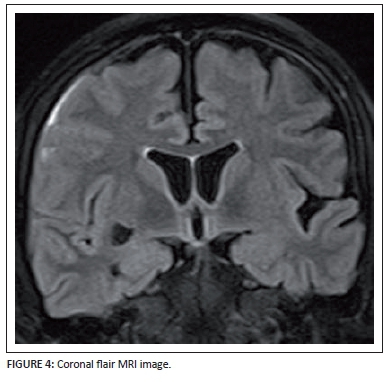

A 40-year-old lady had a CT and an MRI scan of her brain for investigation of severe headache following recent recurrent bowel surgery. The post-operative course was complicated by abdominal wall haematoma, and she required multiple blood transfusions. The background history of multiple previous bowel resections and chronic anti-inflammatory therapy for inflammatory bowel disease was noted.

Describe the relevant imaging findings and formulate the most appropriate clinical diagnosis.